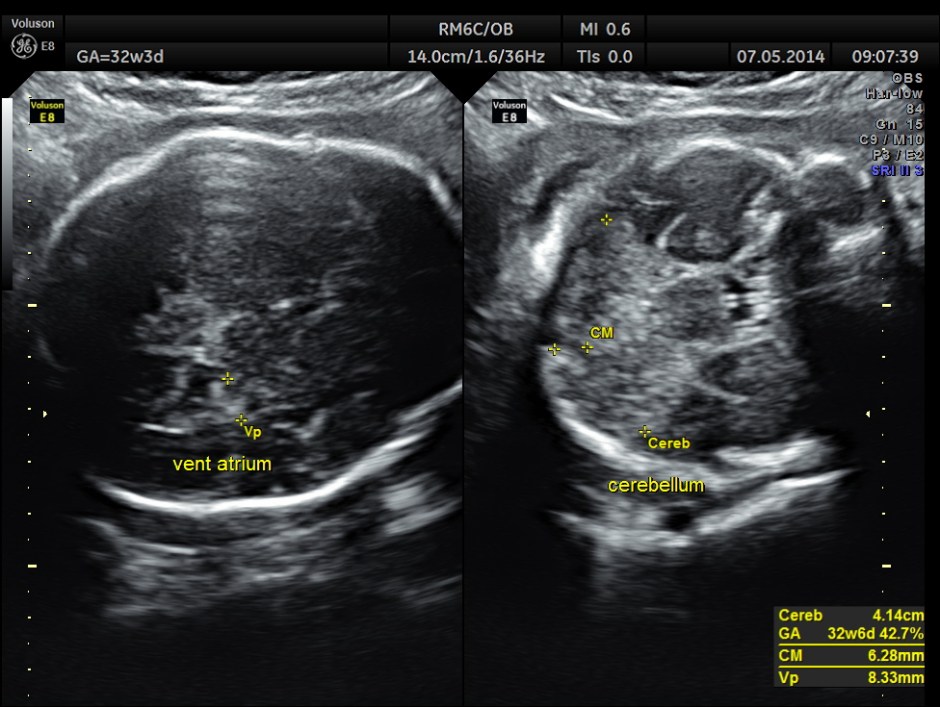

This was a 37 year old lady , a primi gravida referred for evaluation of intra uterine growth restriction. As per LMP the GA was 32 w 3 Days, but as per AUA the GA was 26 weeks . All the long bones were < 5.0 % tile. But cerebellum was 42.7 % tile. There was severe symmetrical growth restriction .